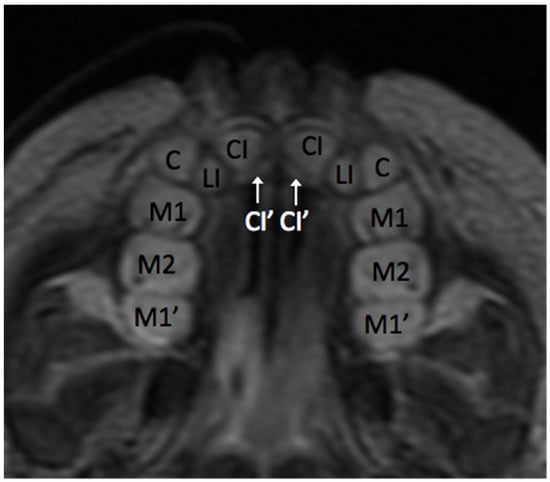

3.1. Anatomy of the Dental Arch